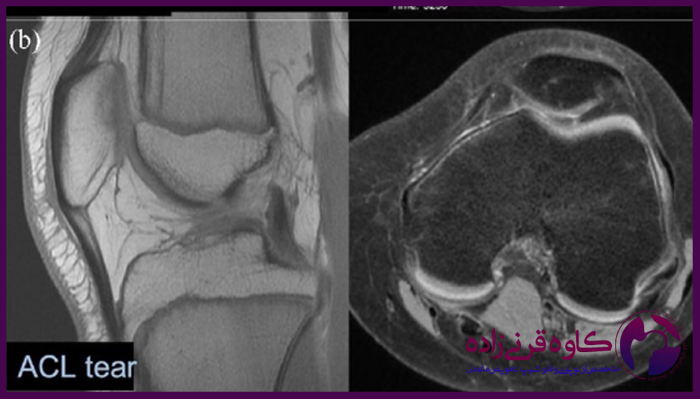

برای تایید تشخیص و بررسی شدت آسیب، معمولا از تصویربرداری به ویژه ام آر آی استفاده میشود که پارگی رباط ها و سایر آسیب ها را به طور دقیق نشان میدهد. در برخی موارد، آرتروسکوپی زانو نیز برای بررسی وضعیت داخلی زانو و تعیین روش درمانی مناسب مورد نیاز است.

عکس ام ار ای پارگی رباط زانو